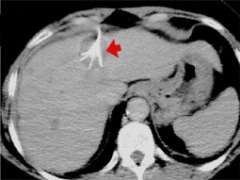

Figure 1: Under CT guidance, a multiple array needle probe is inserted into the center of the liver tumor. After the individual electrodes are deployed from the hollow core of the needle, an alternating current is applied through the needle and electrodes. The tumor cells are killed as the current passes into the tissue at the electrode tips

In radiofrequency ablation, a needle probe under ultrasound, CT, or even MRI guidance is inserted into the center of the liver tumor (fig.1). An alternating current (oscillating in the radiofrequency spectrum, hence the name) is applied through the needle, which passes through tissue to grounding pads placed on the thighs or to another electrode. As the current passes into the tissue at the needle tip, ionic agitation creates frictional heating in the tissue and tumor cells are killed.